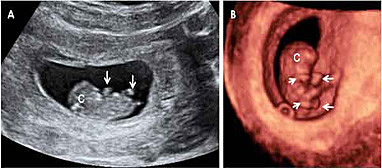

Desarrollo del feto semana 7: Brazos y piernas ya se esbozan

En la semana 7 de embarazo el embrión mide de 5 a 7 milímetros, desde el final de la cabeza (se llama vértex) hasta el final de la "cola", que será en un futuro su coxis; en la ecografía al feto se le mide desde la parte superior de su cabeza hasta la rabadilla. La cabeza aún está muy curvada sobre el pecho y crecerá mucho, ya que el cerebro se desarrolla con rapidez.